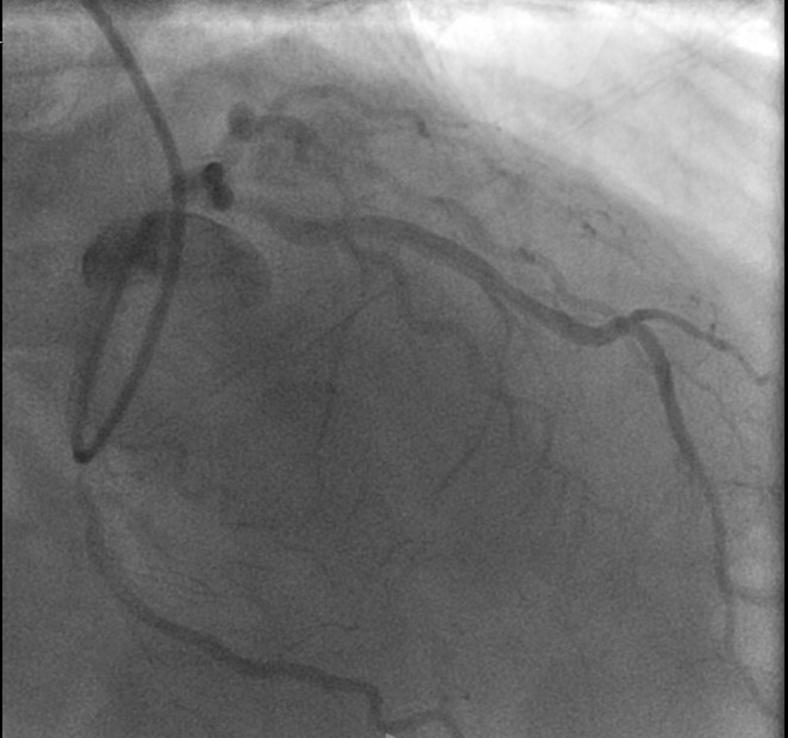

Indocyanine green fluorescence imaging for accurate detection of an intramural coronary artery during robotic coronary artery bypass grafting.

JTCVS Tech. 2025 Jan 28;30:94-97. doi: 10.1016/j.xjtc.2025.01.018. eCollection 2025 Apr.